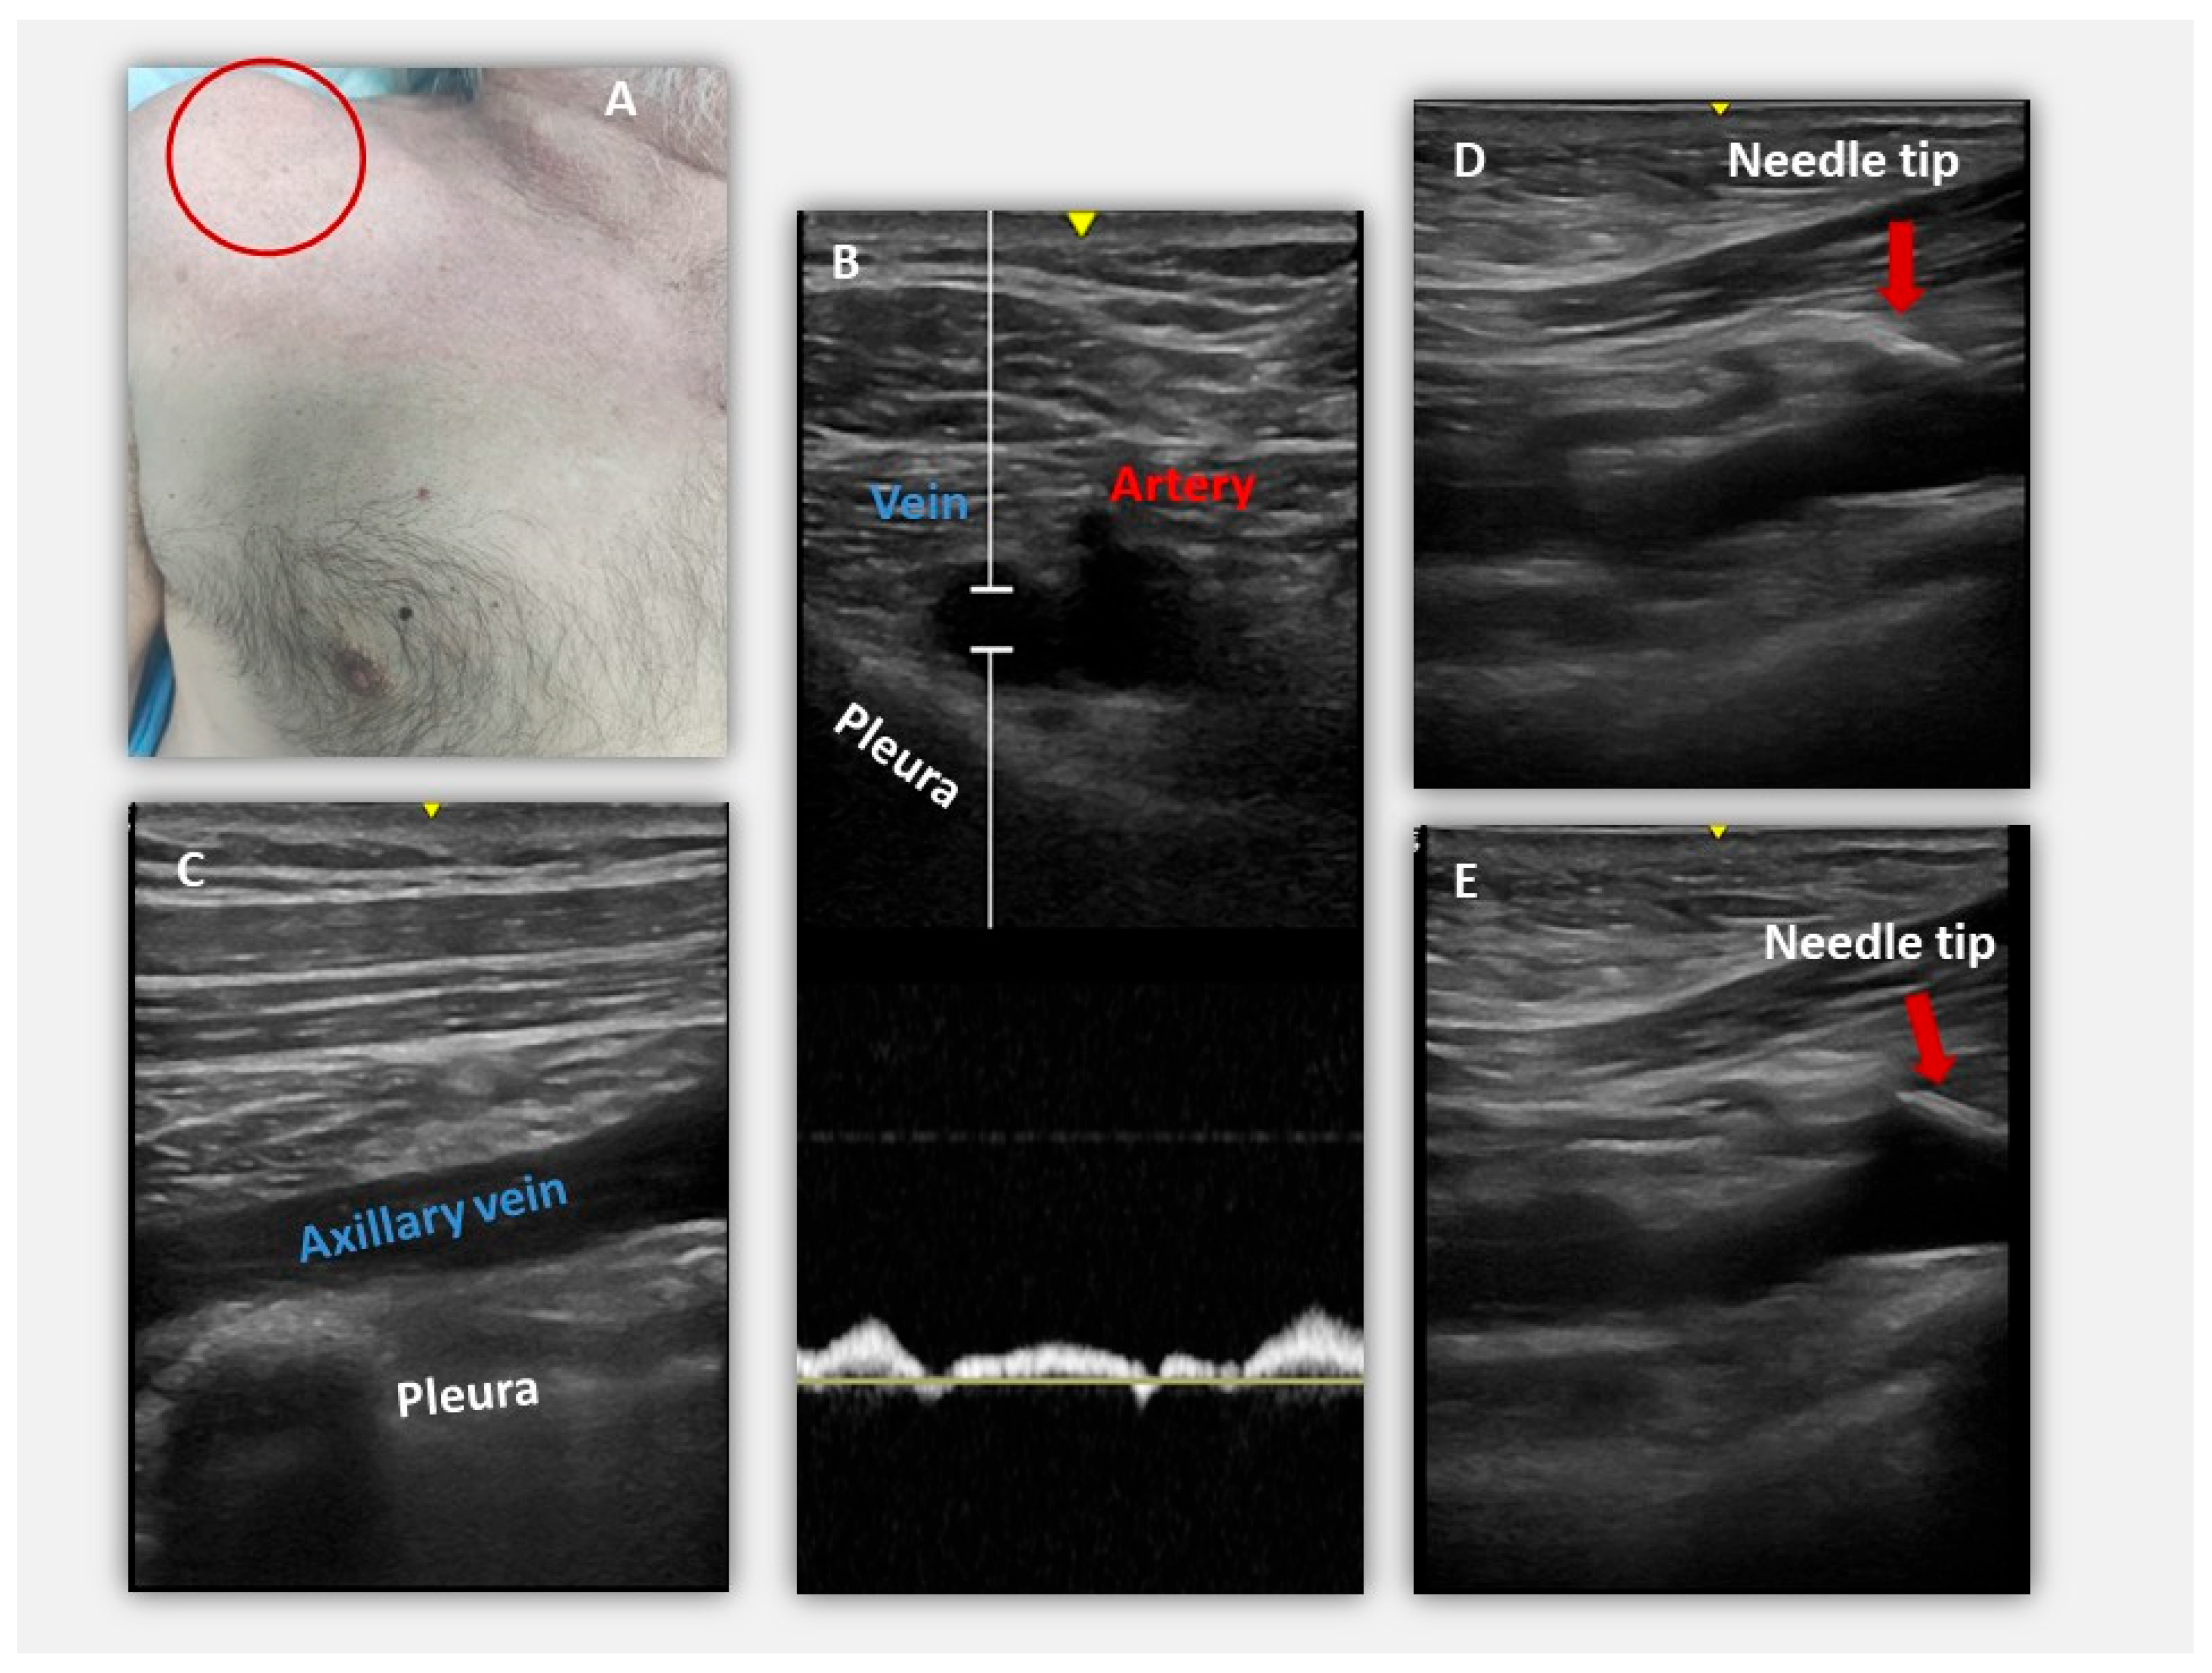

4.2. Ultrasound-Guided Access